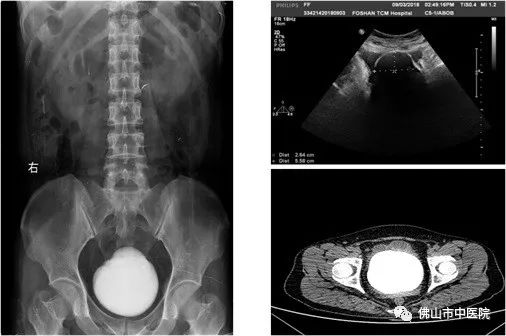

时光飞逝,20年过去了,罗女士逐渐出现排尿困难、尿频、尿急、尿痛,严重影响了日常生活。她开始慌张了,于是来到佛山市中医院就诊,行静脉泌尿系造影检查(IVP)被诊断出膀胱巨大结石。同时合并严重的感染,尿常规:白细胞(沉渣)(WBC)4893.2个/ul,医生建议必须在感染控制后,手术治疗。

麦源医师认为,罗女士的膀胱结石巨大,排尿时随重力的影响,经常会盖住尿道内口,因此出现排尿困难。同时由于结石属于异物刺激容易合并感染,稍有不慎并发脓毒血症,后果很严重。术前他先给罗女士做了膀胱镜检,膀胱镜进入膀胱后,发现巨大结石充满整个膀胱,几乎看不到边界。由于结石导致反复排尿不畅,因此出现泌尿系感染,尿液浑浊。麦源医师分析,如果采取微创手术经尿道手术操作难度大、碎石时间长、黏膜损伤机会增加,不一定能达到微创的效果,容易引发并发症。传统的膀胱切开取石,反而是理想的选择。

经测量,这一结石体积约10.4厘米×9.1厘米×8.7厘米大小,一称竟重达280克。麦源表示,“膀胱结石常见直径在3厘米左右,这么巨大的结石而且长在正常女性身上,我还是第一次处理。”